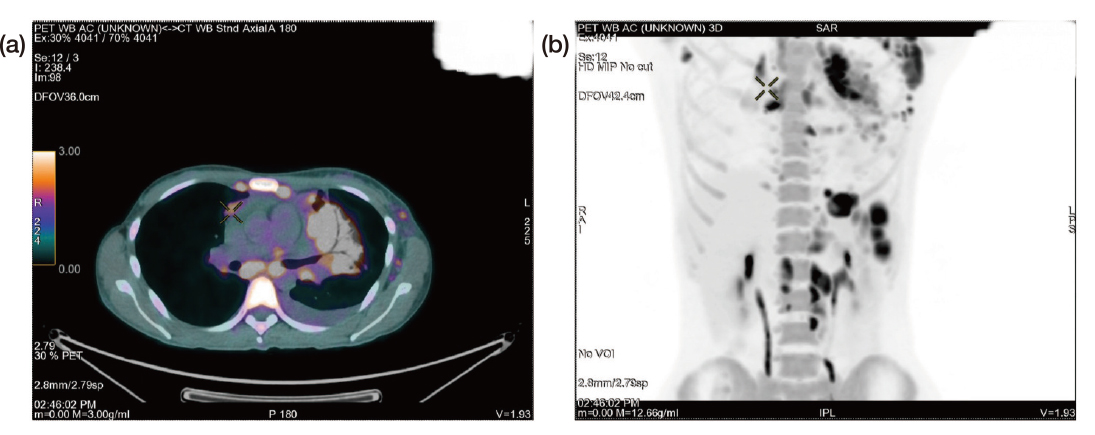

On physical examination, a significant lymphadenopathy was noted, particularly in the supraclavicular and axillary areas. Moreover, the clinical history revealed unintentional weight loss with constitutional symptoms that raised suspicion of cancer, particularly lymphoma. Consequently, patient underwent a PET-CT, which revealed pleural nodules, in addition to significant supraclavicular, mediastinal, and axillary lymph nodes pathology. As a result, an axillary lymph node biopsy was scheduled, however was delayed since the patient acquired the coronavirus disease 2019 (COVID-19) infection, Dr. Sin clarified. Upon her recovery from COVID-19, she finally underwent the axillary lymph node biopsy towards the end of March 2022 and was eventually diagnosed with stage IV classical HL with metastases involving both the lungs and the gastrointestinal tract confirmed by the PET-CT (Figure 4).

Figure 4. PET-CT images of the patient after diagnosis of stage IV Hodgkin¡¦s lymphoma (a) axial view and (b) anterior view (Image provided by Dr. Sin)